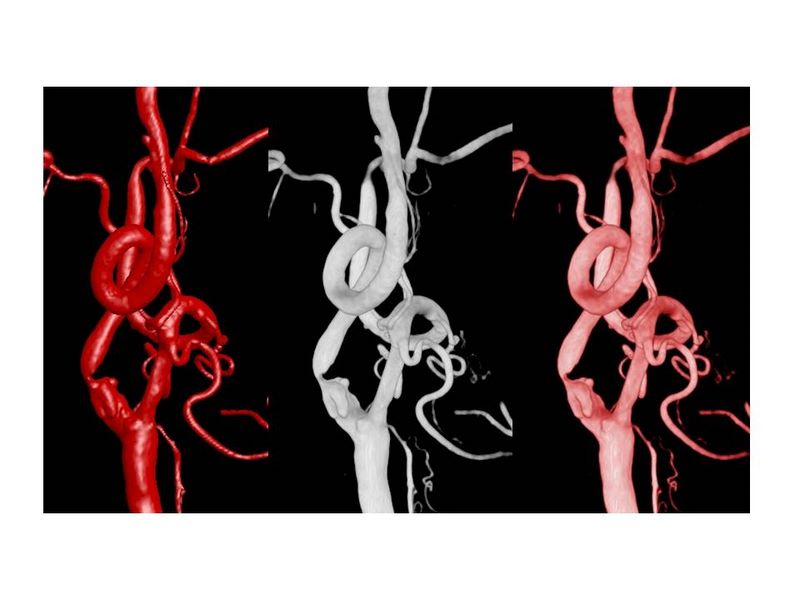

Otro Stent Carotideo